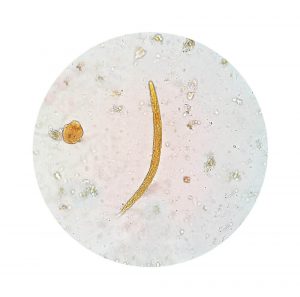

Infektionens sande natur bestemmes let med en analyse af ens fækale stof. Dette vil opdage, om der er aktive amoebaser eller cyster.

Den specifikke årsag til amoebisk dysenteri er en mikroorganisme, der hedder Endameba histolytica. Denne organisme spredes i hele kroppen med afføringen og overføres til andre mennesker, når det forurener mad eller vand. Det påvirker tarmens slimhinde, især tyktarmen.